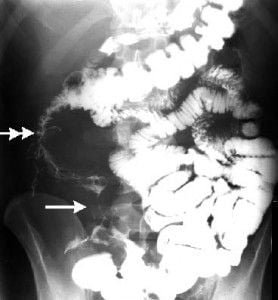

Abdomen, aparato digestivo y via biliarTécnicas de Exploración Radiológica Tránsito del intestino delgado Parte II 28 junio, 2012 Tidito Transito intestinal contraste simple Transito intestinal doble contraste yeyuno e ileon Patologia de Transito intestinal – Enfermedad celiaca Tumor maligno ileon terminalEnfermedad inflamatoria intestinal